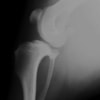

アメリカンコッカースパニエル 5歳

半年にわたる左後肢の跛行が認められるとのことで来院されました。触診にて左膝関節の疼痛、内側部の腫脹、膝蓋骨の内方脱臼を認めました。レントゲン検査にてfat pad signを伴う関節炎が認められたことから、前十字靭帯断裂と膝蓋骨内方脱臼( GradeⅢ)の併発と診断し、手術を行いました。術中の関節鏡検査にて前十字靭帯の完全断裂を確認、関節液検査にて感染を除外した後、TPLOと、滑車溝形成を始めとした膝蓋骨脱臼整復術を実施いたしました。

術前側面像

術前正面像

術後側面像

術後正面像

術前に25°であったTPAは、TPLO実施により7°に矯正されました。症例の歩行状態は良好です。